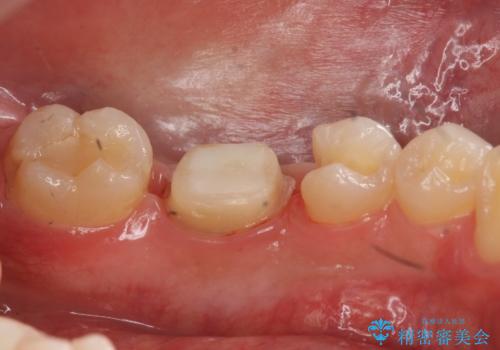

- 他の歯を治療中にレントゲン写真を撮ったところ虫歯を発見。

どうせなら1つ奥の銀歯も白くしたいとのご希望があり、2本ともセラミックにて治療をしていくことになりました。

- 右下6 仮歯+ジルコニアクラウン(スタンダード) 11000円×1本+110000円×1本 右下5 セラミックインレー 77000円×1本費用は治療当時の料金となります

虫歯治療に加え、奥の銀歯も同時にやり替えました。